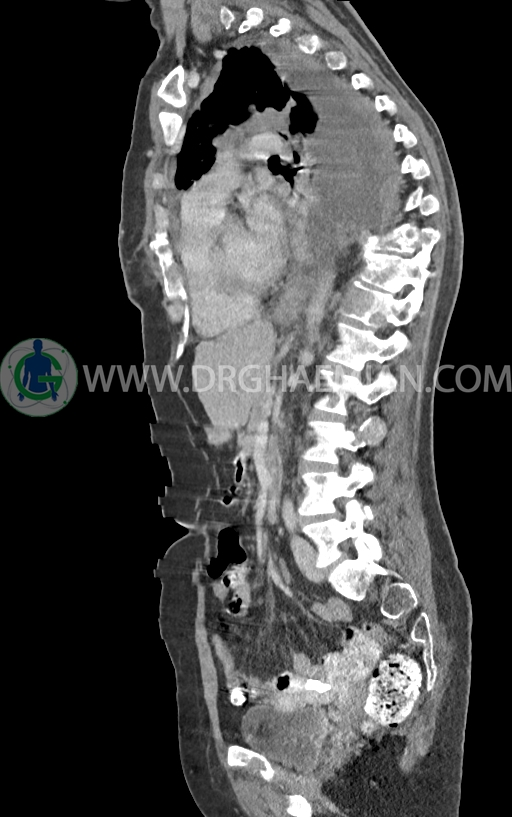

–توده نسج نرمی بسیار بزرگ به حداکثر دیامتر 82mm همراه با مارژین لبوله در پستان راست دیده شد که همراه با گسترش و درگیری پوست و نیپل بوده و مطرح کننده ضایعه تومورال و بدخیم می باشد.

–این توده در قسمت هایی عضله پکتورالیس این سمت را abut کرده است.

– ندول های نسج نرمی اقماری متعدد در مجاورت فوقانی این توده با حداکثر دیامتر کمتر از 17mm

– تعدادی لنف نود هتروژن و irregular با حداکثر SAD<12 در آگزیلاری راست